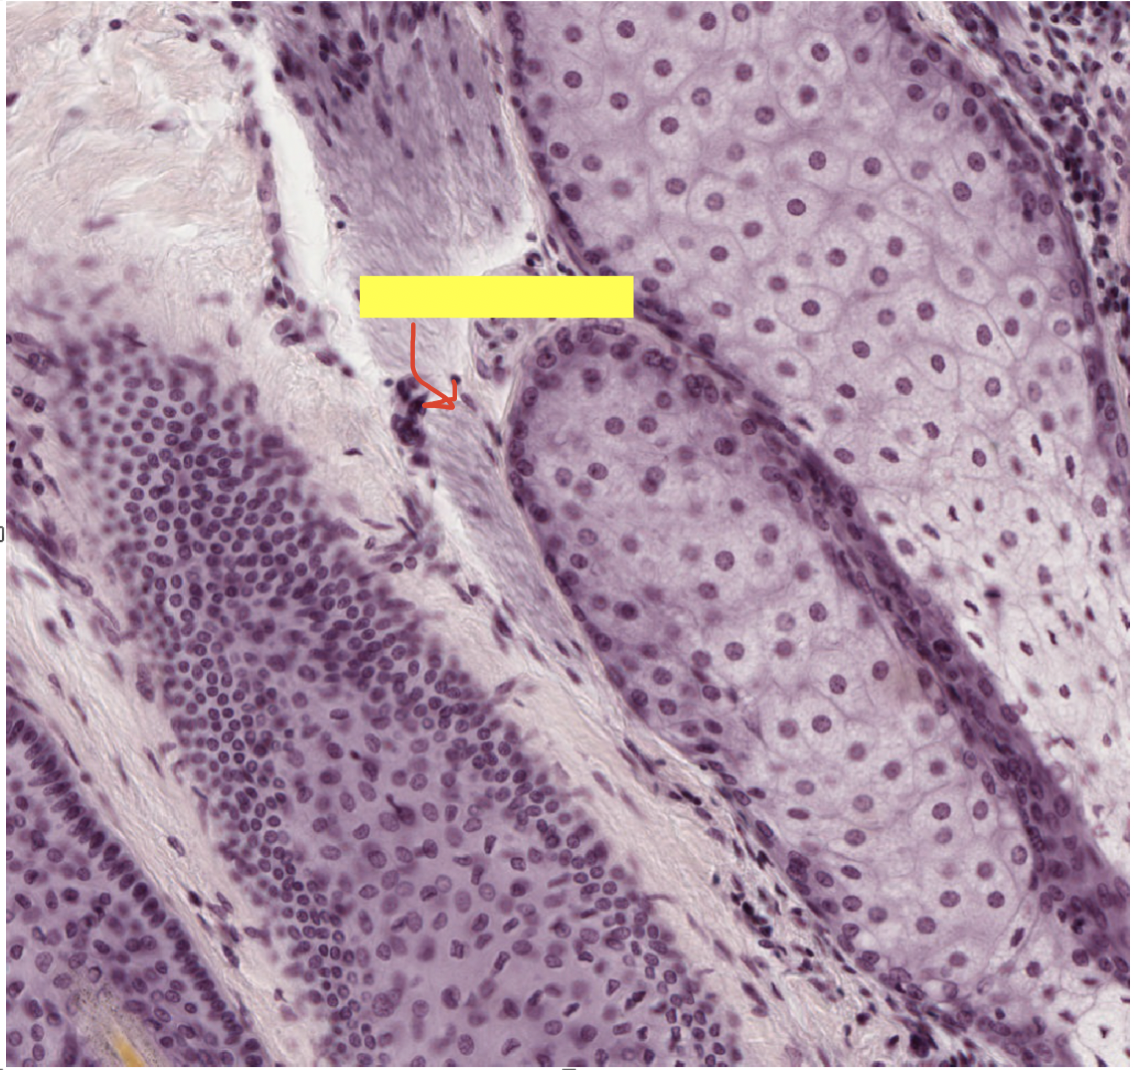

what type of muscle is arrector pili muscle